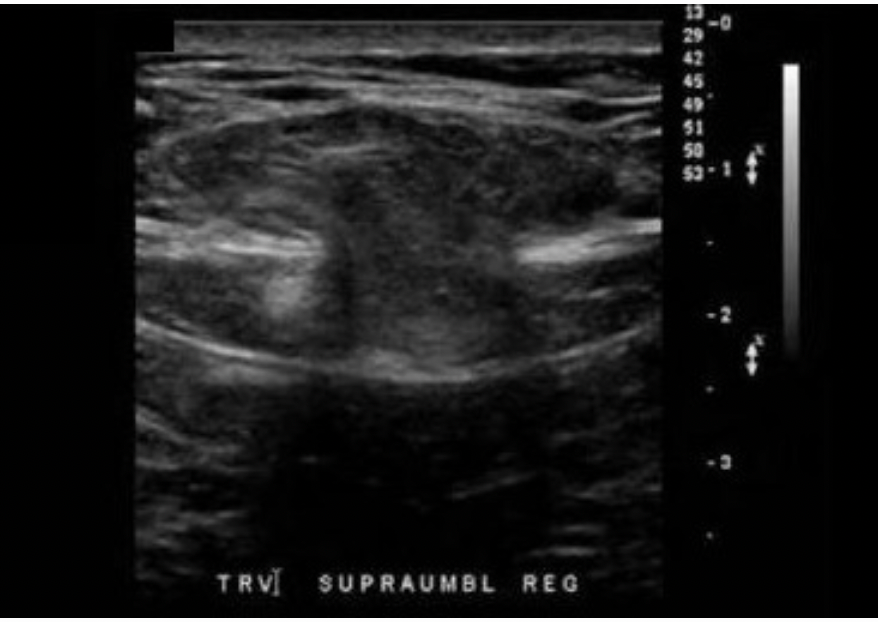

A 50yr old male presents with paraumbilical pain and a palpable mass. The findings on the image are most suggestive of:

D. Abdominal wall hernia with bowel protrusion

The image demonstrates an opening in the peritoneum and muscular fascia of the abdominal wall with a "mushroom cloud" of intestine extending anteriorly through the herniation. The Valsalva maneuver is helpful in evaluating the presence/absence of bowel protruding through a herniation in the abdominal wall. The increase in intra-abdominal pressure should force the bowel through the opening and peristalsis should occur upon release.